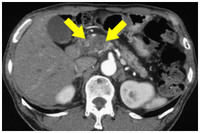

膵臓癌って末期でもctや超音波検査などで見つからないことってありますか 大体 Yahoo 知恵袋